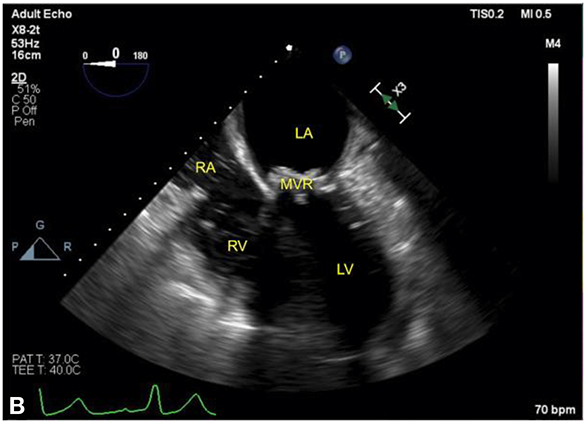

Figure 12.3.: Acute Regional Pericardial Effusion: Left Atrial Compression.

Acute regional pericardial effusion: left atrial compression. A and B show an example of regional pericardial effusion posterior to the heart, compressing the left atrium (LA), is shown. The heart is shown in a midesophageal four-chamber view, with (A) rotated leftward to center the view on the localized pericardial effusion (dotted line). In both views, the left ventricle (LV) is partially obscured by shadowing artifact from a bioprosthetic mitral valve replacement (MVR). A. The LA is partially compressed by the effusion. B. The same heart following decompression, showing restoration of LA size, is seen. Agitated blood can be seen in the right atrium (RA) and right ventricle (RV) during intravenous fluid administration.